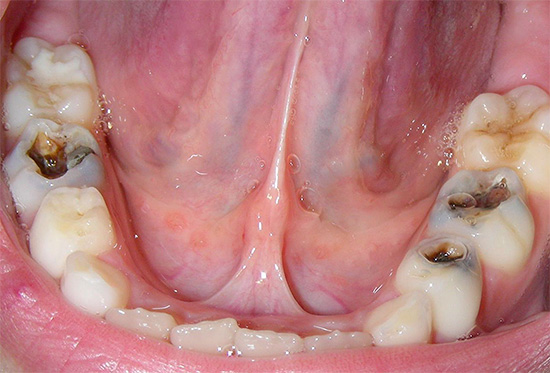

Ad esempio, nella foto sotto - carie generalizzata:

E questa foto mostra un altro esempio di come i denti sono stati colpiti carie generalizzata. Questa è una forma molto pericolosa della malattia, che minaccia una persona con la perdita di una parte significativa dei denti, la depulpazione (rimozione dei nervi) e l'installazione di corone: